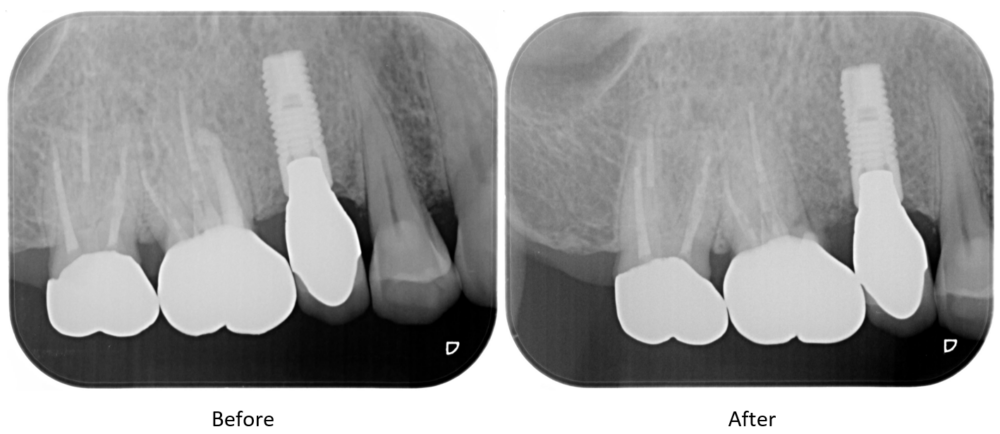

症例2

| 患者様データ | 70代 男性 |

| 来院時の主訴 | 「右上の歯が噛むと痛い。」 |

| 医院の診断 | 近心頬側根の歯根破折 |

| 通院期間 | 3か月 |

| 来院回数 | 4回 |

| 治療費 | 総額:歯根切除法180,000円(税抜) |

| リスクと副作用 | ①根管治療歯は長期的には破折するリスク ②長期的なメインテナンスが必要 |

| ここがこだわりのポイント!☝ |

右上の奥歯には3つの根っこがあり、そのうちの2つは健康で1つだけが破折していました。破折している歯根のみを切除し抜歯することで、残った歯を保存することができました。 |